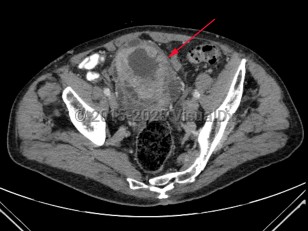

Psoas abscess

Pyelonephritis

Spinal epidural abscess

Uterine fibroidsUterine fibroids

Abdominal aortic aneurysmAbdominal aortic aneurysm

Bladder cancerBladder cancer

EndometriosisEndometriosis